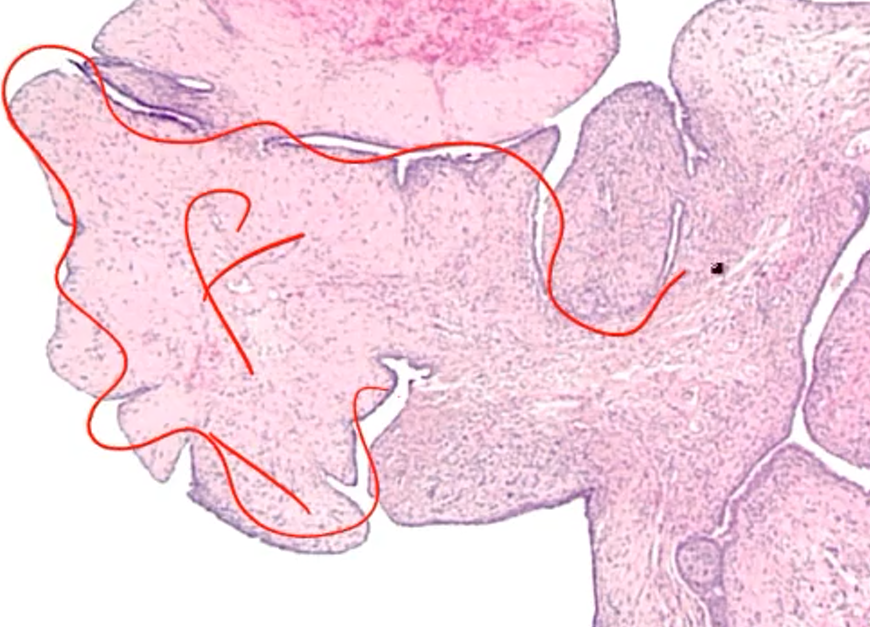

What type of pathology is indicated here?

Phyllodes tumor

Note the “leaf like” projections